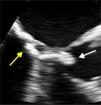

A 79-year-old woman was referred to our department because of suspected angina. The electrocardiogram showed ventricular repolarization abnormalities in the lateral wall. Transthoracic echocardiography showed preserved biventricular systolic function, without wall motion abnormalities, a mitral valve with normal functional area and marked calcification of the annulus, and on the ventricular side a hyperechoic, threadlike and highly mobile mass, protruding into the left ventricular outflow tract, causing a dynamic gradient of 24 mmHg (Video 1). Transesophageal echocardiography (TEE) showed a mass adjacent to the posterior annulus of the mitral valve, measuring about 25 mm×5 mm (Figure 1; Video 2 and 3). Computed tomography confirmed a large calcified mass attached to the ventricular side of the mitral valve (Figure 2). No mass was observed on cardiac magnetic resonance imaging, probably due to its marked mobility. Myocardial perfusion scintigraphy showed evidence of inferolateral ischemia and cardiac catheterization revealed left main and three-vessel disease. Bypass surgery was performed and the intraventricular tumor was removed (Figure 3). Histology confirmed the diagnosis of calcified amorphous tumor (Figure 4).